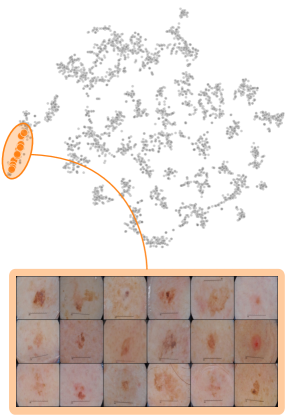

In this section, we leverage latent bias representations, either via directions or individual neurons, to retrieve biased samples and measure how well bias samples are separated from clean samples. We compute bias scores as defined in Eq. 1 by projecting latent activations onto the bias direction. As we are mostly interested in the ranking capabilities, i.e., artifact samples should be assigned higher bias scores than clean samples, we measure Area Under the Receiver Operating Curve (AUROC) and Average Precision (AP), considering both real and controlled artifacts. For real artifacts, we evaluate retrieval using existing artifact labels, while we have ground truth information for controlled experiments. We train CAVs using Support Vector Machines (SVMs) on different layers of VGG16 and ResNet50 models for all datasets, reporting AUROC and AP on unseen test samples. Note, that while Pahde et al. [58] claim that classifier-based CAV computation can yield imprecise concept directions, they argue that SVM-CAVs are superior for predicting concept presence, the main goal of this experiment. In Fig. 7, we show the results for different layers of VGG16 and ResNet50 using single neurons (dashed line) and CAVs (solid line) as bias representation. Best neurons are selected using the validation set. The results indicate that CAVs generally outperform single neuron representations for sample retrieval, and the layer choice is crucial depending on the bias type. For instance, while CAVs for layers closer to the model heads can detect pacemaker samples, they fail for earlier layers.

We further plot the distribution of CAV-based bias scores for biased and clean samples for the real-world artifacts ruler (ISIC2019) and pacemaker (CheXpert) in Fig. 8. We compute bias scores using the best performing CAV per artifact and use latent activations after the residual block of the ResNet50 model for ruler, and the convolutional layer of the VGG16 model for pacemaker. We show samples corresponding to the bias score in the top-1 and -99 percentiles of each set. Samples near the decision boundary are particularly interesting, as they may arise from labeling errors. Both examples demonstrate the retrieval of unlabeled artifact samples. The distributions of bias scores for additional artifacts are shown in Appendix A.6.2.